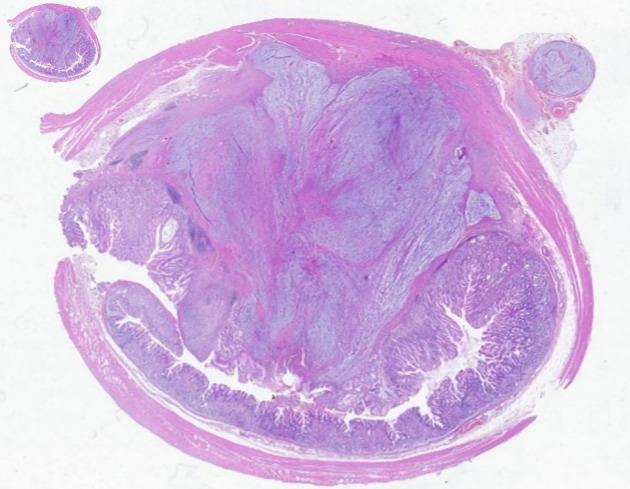

Gastric schwannomas and gastrointestinal stromal tumors (GISTs) are two types of mesenchymal tumors, which represent a group of rare tumors of the gastrointestinal tract. The differential diagnosis between these two tumors is difficult given their very similar appearance and clinical features. The authors present a case of a 63-year-old man with melena and epigastric pain. An upper digestive endoscopy was performed, revealing an ulcerated gastric subepithelial lesion suspected to be a GIST. Further imaging with a computed tomography (CT) scan revealed a well-defined hypodense solid nodular mass, with homogeneous enhancement, measuring 22 × 18 mm, on the anterior wall of the transition between the body and gastric antrum, situated within the submucosal layer. The patient subsequently underwent a laparoscopic atypical gastrectomy, which proceeded without complications. The pathological examination of the excised lesion confirmed it to be a gastric schwannoma, with complete excision. This case report illustrates a rare cause of gastrointestinal bleeding, that requires immediate action, and en bloc resection is usually curative. Given the excellent prognosis after complete resection, a correct diagnosis is essential.